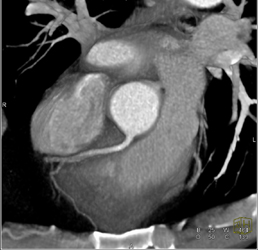

Diagnosis

Diseased LAD